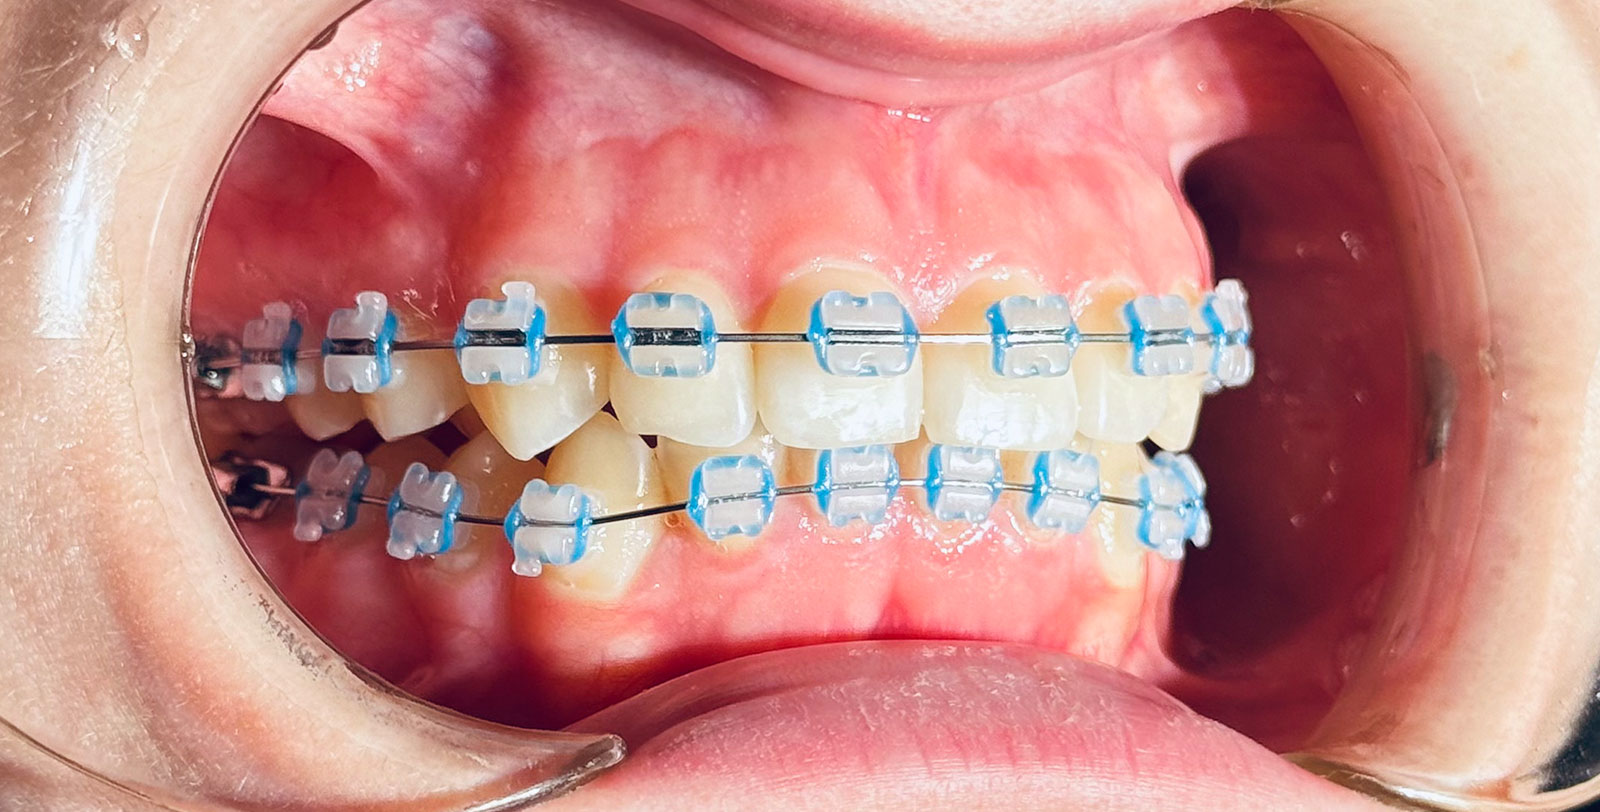

За конструкцією брекети з кераміки можуть бути:

- лігатурні: з наявністю лігатур (гумок)

- безлігатурні або самолігуючі: замість лігатур – спеціальні кліпси (тривалість ортодонтичного лікування скорочується, але і вартість таких систем вище).